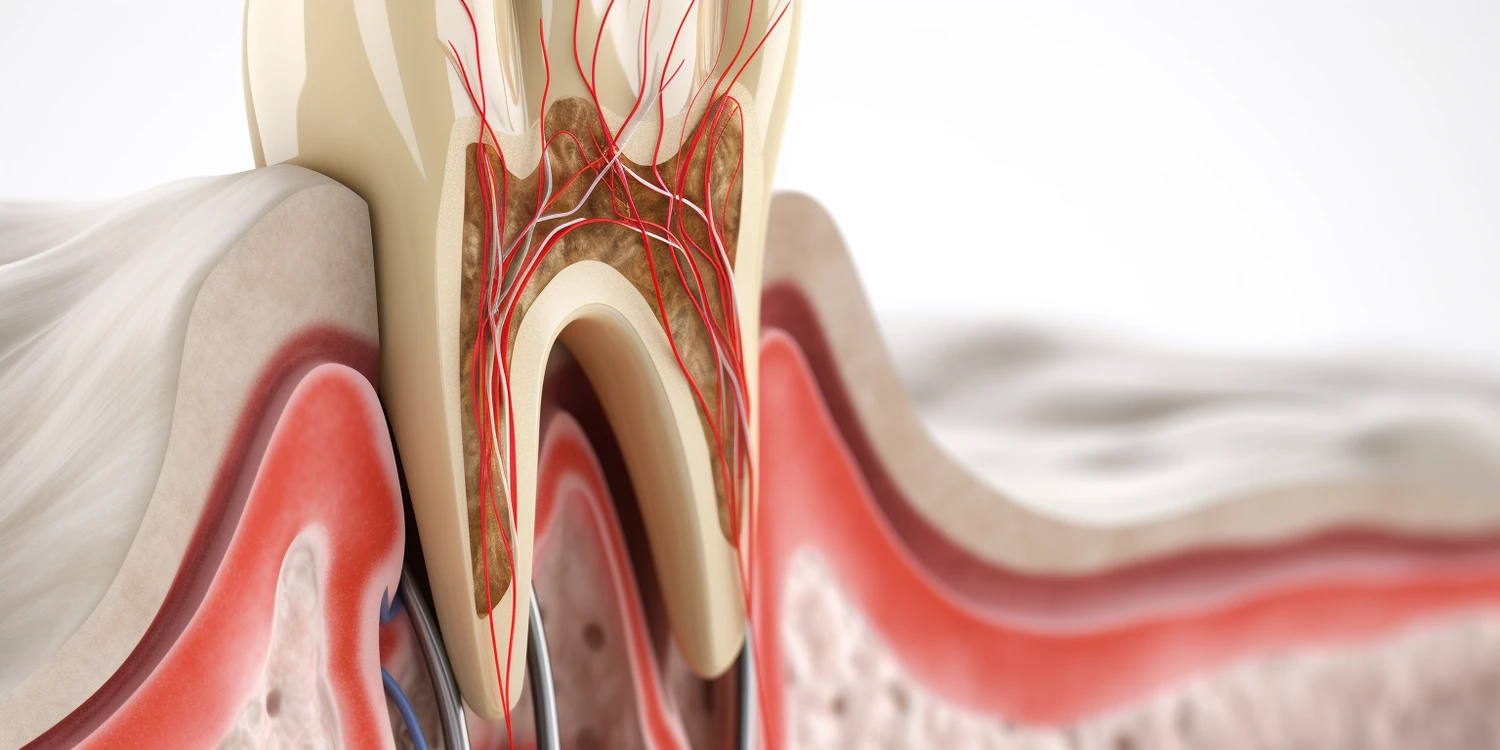

Leczenie kanałowe, znane również jako endodoncja, to procedura stomatologiczna mająca na celu uratowanie zainfekowanego lub uszkodzonego zęba. W trakcie tego zabiegu dentysta usuwa miazgę zęba, która może być źródłem bólu oraz stanu zapalnego. Miazga to tkanka zawierająca naczynia krwionośne oraz nerwy, a jej usunięcie pozwala na oczyszczenie wnętrza zęba. Po usunięciu miazgi dentysta dokładnie dezynfekuje kanały korzeniowe, aby usunąć wszelkie bakterie oraz resztki tkankowe. Następnie kanały są wypełniane specjalnym materiałem, co zapobiega dalszym infekcjom. Leczenie kanałowe jest często jedynym sposobem na uratowanie zęba przed ekstrakcją, a jego celem jest przywrócenie pełnej funkcji zęba oraz eliminacja bólu. Warto zaznaczyć, że pomimo skomplikowanej procedury, leczenie kanałowe jest zazwyczaj bezbolesne dzięki zastosowaniu znieczulenia miejscowego.

Proces leczenia kanałowego składa się z kilku kluczowych etapów, które są starannie zaplanowane przez dentystę. Pierwszym krokiem jest dokładna diagnoza, która obejmuje badanie kliniczne oraz zdjęcia rentgenowskie mające na celu ocenę stanu zęba i otaczających tkanek. Po ustaleniu diagnozy pacjent otrzymuje znieczulenie miejscowe, aby zapewnić komfort podczas zabiegu. Następnie dentysta przystępuje do otwarcia korony zęba w celu uzyskania dostępu do miazgi i kanałów korzeniowych. Kolejnym krokiem jest usunięcie chorej miazgi oraz dokładne oczyszczenie wnętrza zęba za pomocą specjalistycznych narzędzi endodontycznych. Po zakończeniu oczyszczania dentysta wypełnia kanały materiałem uszczelniającym i zamyka otwór w koronie zęba. W niektórych przypadkach konieczne może być wykonanie dodatkowej odbudowy zęba za pomocą korony protetycznej.